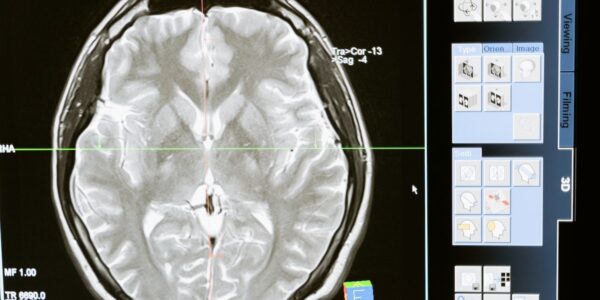

Egészséges agy: így vigyázz rá

Az agy minden életfunkciónk kiindulópontja. Ha vigyázunk rá, tápláljuk fizikai és mentális értelemben, sokkal hosszabb és boldogabb életet élhetünk.